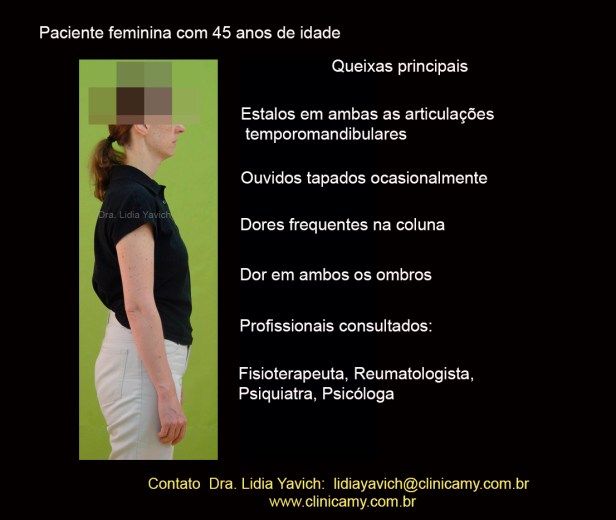

Paciente de sexo feminino com 45 anos de idade foi encaminhada para a clínica pela sua fisioterapeuta com queixas de dor de cabeça, dor na região cervical e escapular e contraturas musculares na mandíbula.

Paciente de sexo feminino com 45 anos de idade foi encaminhada para a clínica pela sua fisioterapeuta com queixas de dor de cabeça, dor na região cervical e escapular e contraturas musculares na mandíbula.

A paciente também refere deslocamento mandibular ao tocar o violino e dor em ambas as articulações temporomandibulares.

A paciente também refere estalos em ambas as articulações temporomandibulares, e ocasionalmente sensação de ouvidos entupidos.

A paciente também refere estalos em ambas as articulações temporomandibulares, e ocasionalmente sensação de ouvidos entupidos.

Dores frequentes na coluna e em ambos os ombros.

Na época a paciente já tinha consultado fisioterapeutas, reumatologista, psiquiatra e psicólogo.